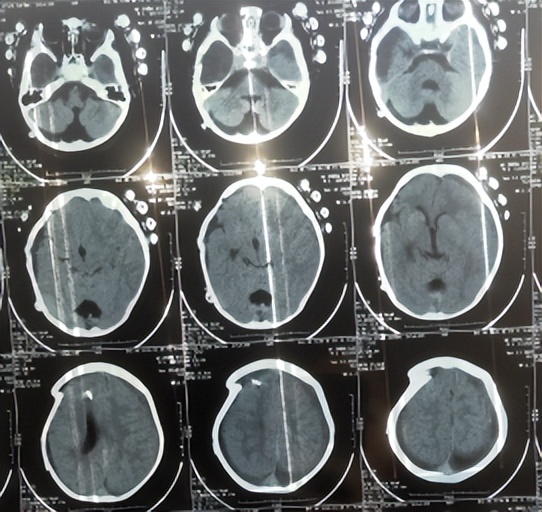

患儿2018年2月份,早产1月,剖宫产出生,出生后未见异常;患儿3个月大起,家属发现患儿头围较同龄幼儿大点,未给予重视;直到7个月大时,因发育迟缓自己不能坐,且头围进行性增大,于2018年9月11日,至当地第1家医院陕西省西康市白河县某医院,检查头颅CT发现双颞叶蛛网膜囊肿、脑积水( 图-1 )。

图-1: 2018年9月11日头颅CT